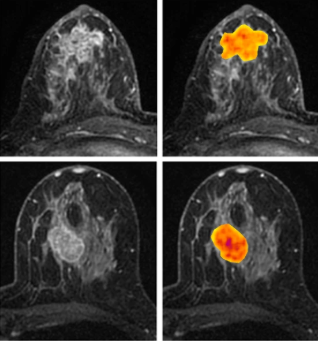

Predicting #breastcancer risk of recurrence with #MachineLearning: bit.ly/2nDOm3X #breastcancerawareness #WednesdayWisdom Georgia State University Emory University Uni of Nottingham #WeAreUoN Cedars-Sinai